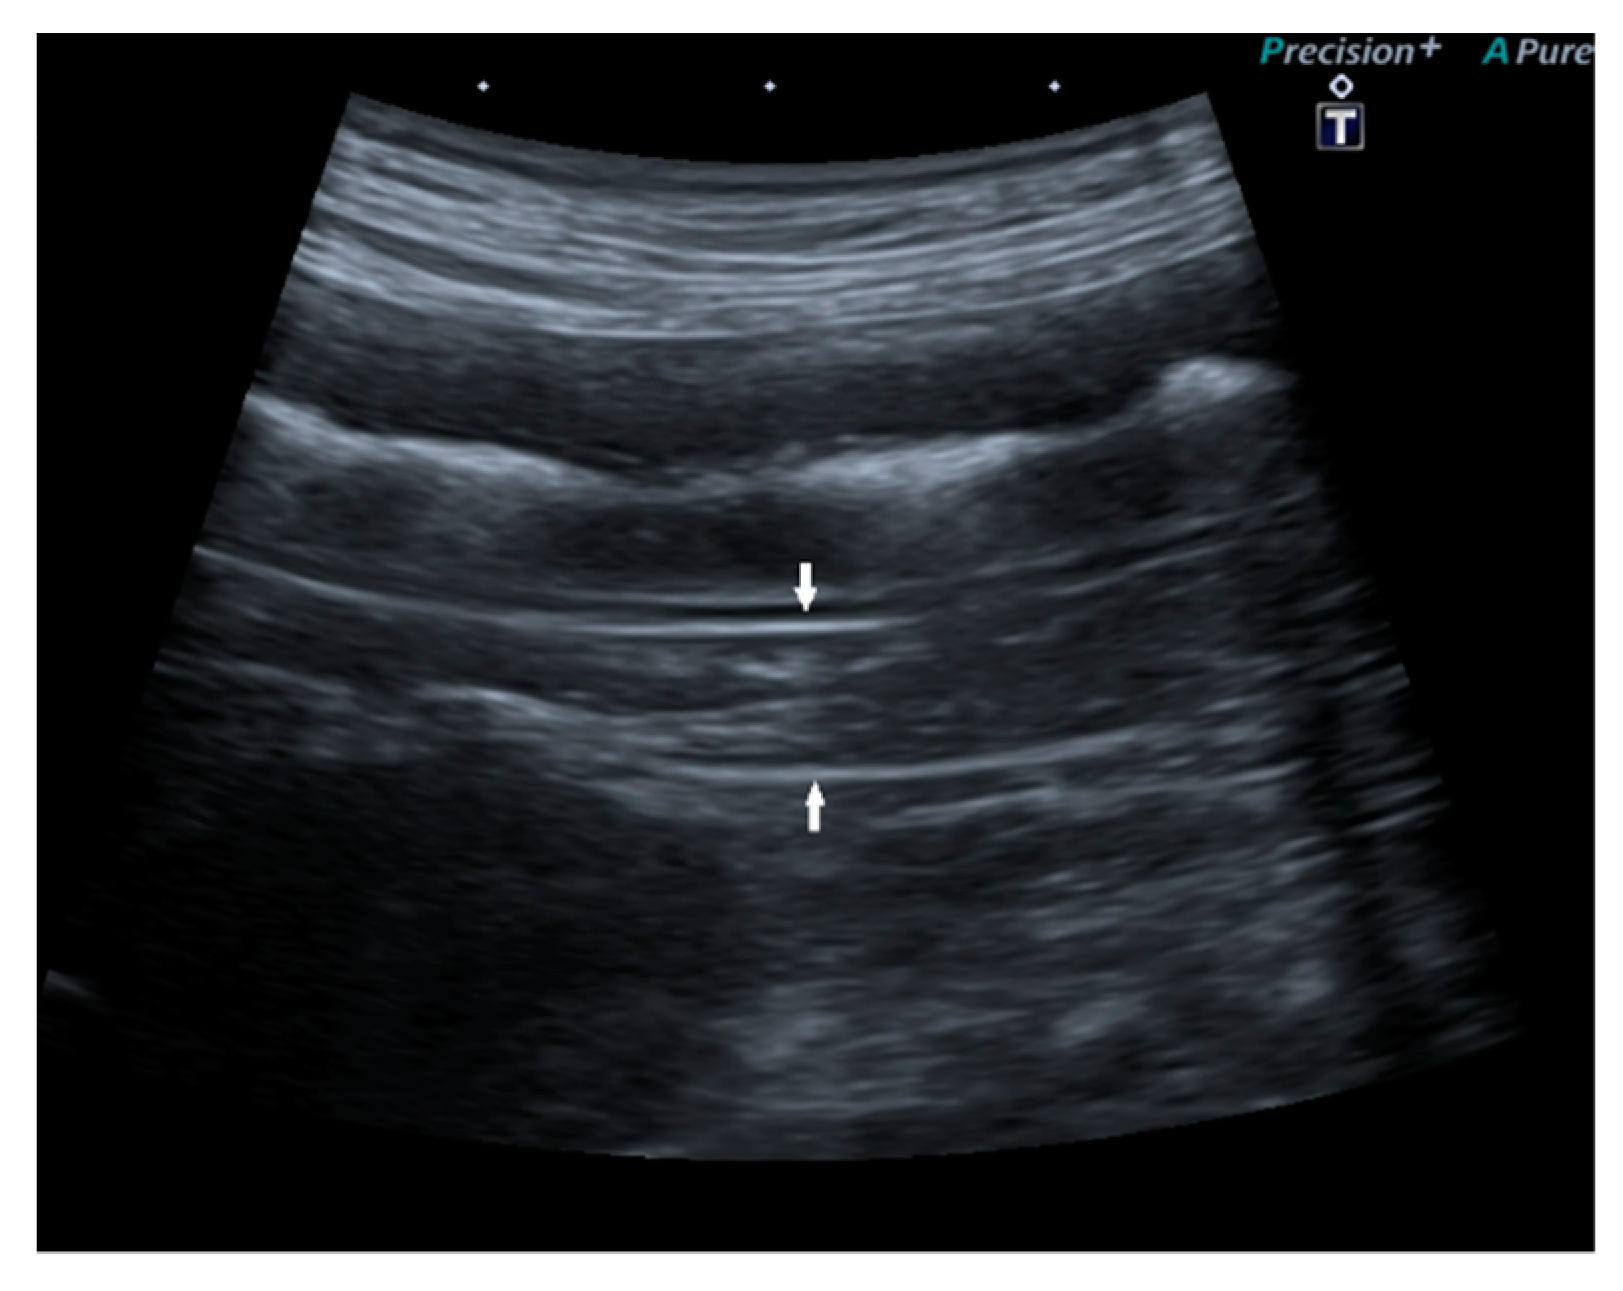

In 15/22 dogs (68%), the pancreas had a normal ultrasound appearance, with normal shape, margins, and echogenicity, homogeneous echotexture, and without pancreatic duct abnormalities (Figure 2).

Figure 2.

Ultrasound image of the right pancreatic limb with normal shape and echogenicity, regular margin, and homogeneous echotexture.